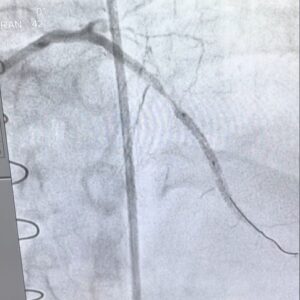

We recently performed a Thoracic Endovascular Aortic Repair (TEVAR) on a 22-year-old male presenting with uncontrolled hypertension.

“`Diagnostic evaluation revealed coarctation of the aorta with a significant translesional gradient of 50 mm Hg, along with a post-stenotic aneurysm.

The final outcome was excellent, with complete resolution of the translesional gradient.